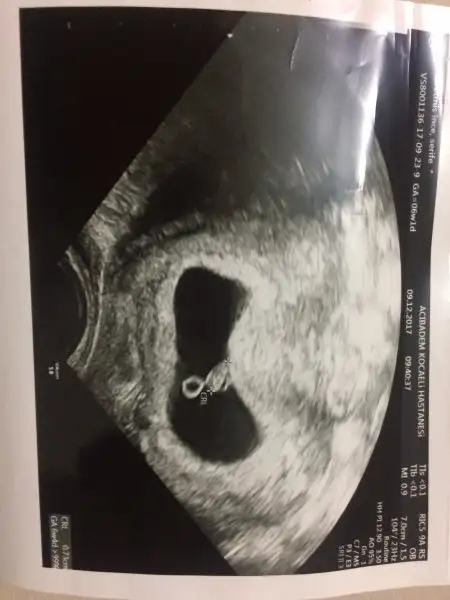

Selam kızlar bende bugün doktora gittim önden gidiyoruz 8+5 deyim. Benim akıntılarım vardı. Son 2 günde kaşıntı olunca doktorum onuda kontrol etti :KK43: mantar... neyse bebek gayet iyiymiş, hareketli de kendisi. Kollar bacaklar çıkmış :) teyzesi bir cinsiyet yorumu da biz alalım. Mantar için bakılınca ultrasonumda vajinal oldu. interiorarchitect interiorarchitect

Maşallah acaba ultrason vajinal oldugu icin mi boyle net? Benim 7+2de karindan ultrasonum var.bebeim o kadar silikki..:110:

Ay öaşallah yaaaa, nasıl net maşallahhhh, benim de bu sabah kanamam oldu , gittik , kan sulandırıcı yapar kanama deid de bebek iyi dedi, ama çok moralim bozuldu , kan görmek çok üzdü beni , buna da şükür ki bebiş iyi, canım senin son adet tarihin ne ? Benim ultrason fotom böyle net değil , benimki 24 ekim , mantar için ne dedi dr

Canım daha hiç karından ultrasonum yok benim o yüzden pek bilemiyorum ama 6+5 te benimde öyle onuda yükledim. 2 haftada çok değişmiş.